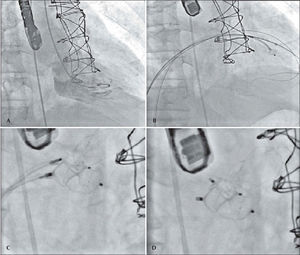

In 2011, the 2D transthoracic echocardiography showed mechanical prostheses with normal disc excursion and preserved left ventricular systolic function despite the severe paravalvular mitral regurgitation, moderate right ventricular dysfunction, and pulmonary artery systolic pressure estimated at 90mmHg. In that same year, the team proposed to the patient a percutaneous correction of the periprosthetic defect, which was performed on July 6, 2011 (Figure 1). The procedure was performed under general anaesthesia and was initiated by puncturing the right femoral vein and the left femoral artery with 7F and 6F introducers, respectively, followed by the administration of a 100 U/kg dose of unfractionated heparin. Subsequently, a transseptal puncture was performed using a Brockenbrough needle and an 8F Mullins sheath. A hydrophilic guidewire was introduced through the Mullins sheath with a 0.035-inch Radiofocus Terumo® 260cm angle tip (Terumo Medical Co. – Tokyo, Japan), maintained in the left atrium. Using this guidewire, the Mullins sheath was exchanged for a Fu Star® sheath (Lifetech Scientific – Shenzhen, China), through which the paravalvular defect was found and the 0.035-inch Radiofocus Terumo® 260cm angle tip guide wire was steered past the defect with the aid of 3D transesophageal echocardiography. The Fu Star® Lifetech sheath was exchanged with a therapeutic Multipurpose 7F catheter (Johnson & Johnson Co. – Miami, FL, USA), which was guided past the paravalvular defect and through which another 0.035-inch Radiofocus Terumo® 260cm angle tip guide wire was introduced. This catheter was removed and two Multipurpose 7F catheters were introduced separately through the two guide wires that were guided past the paravalvular orifice. Then, two Amplatzer™ Vascular Plug III (numbers 10 and 8) prostheses were implanted through the 7F multipurpose catheters with continuous monitoring by 3D transesophageal echocardiography, which guided the correct prosthesis positioning and release. At the end, the disappearance of the paravalvular defect was demonstrated. There were no complications during the procedure. The patient was extubated in the catheterisation laboratory and observed for 2 hours before discharged to the infirmary.

– In A, catheters in the left ventricle after moving past the mitral paravalvular orifice. In B, the positioning of the prostheses, with guidewire in the left ventricle. In C, placement of the prostheses, starting their release. In D, the release of the prostheses. In E and F, the final result.